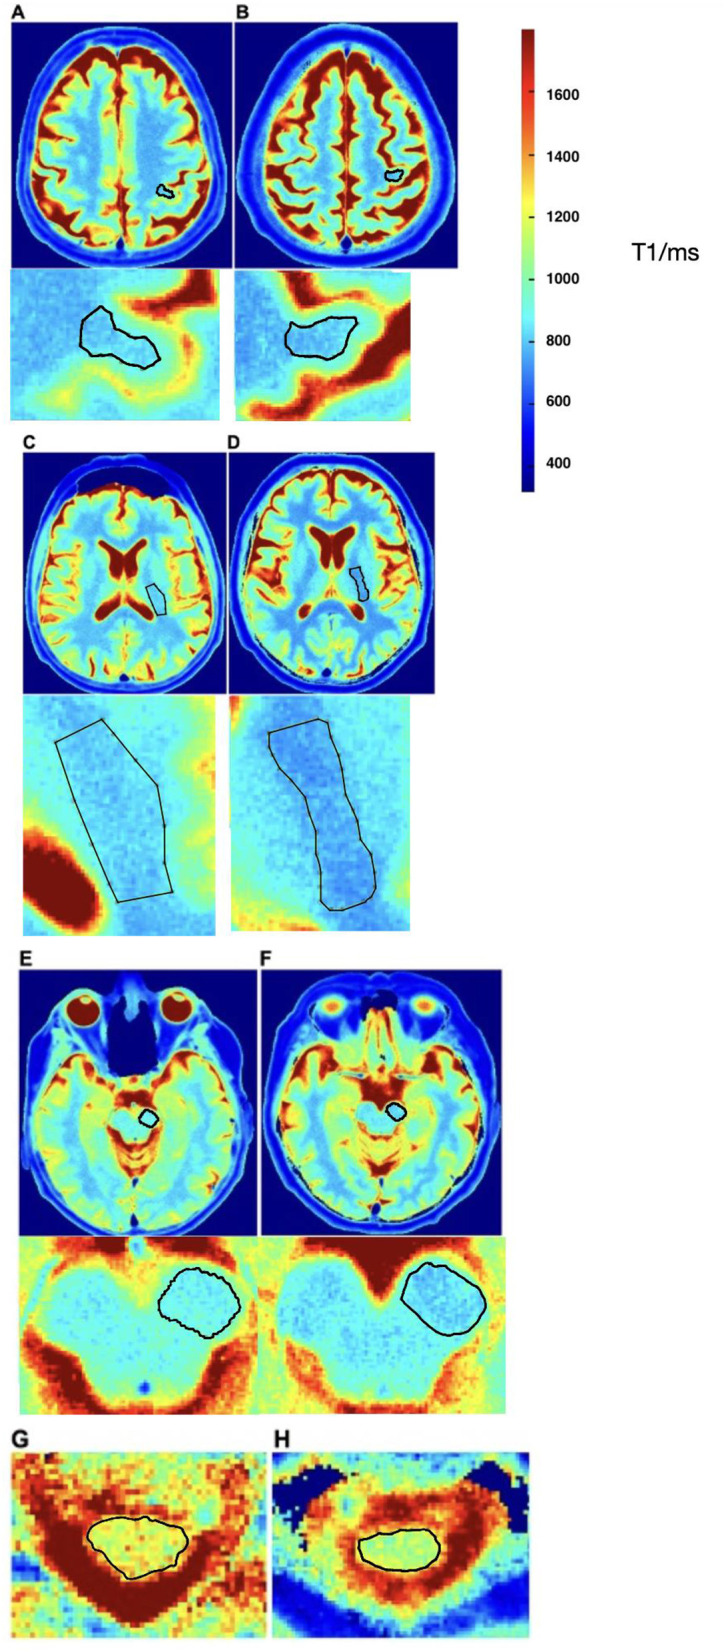

Methods: We investigated the diagnostic potential of a novel T1-mapping method based on real-time MRI with 0.5 mm in-plane resolution and 4s acquisition time per slice. The study included patients aged 18 to 90 years who met the revised El Escorial criteria for at least possible ALS. T1-relaxation times were measured along the corticospinal tract in predefined regions of interest.

Results: Twenty-nine ALS-patients and 43 control group patients (CG) were included in the study. Median ALS Functional Rating Scale revised (ALSFRS-R) was 37 (IQR, 35-44) points and the mean duration from symptom onset to MRI was 21 ± 17 (SD) months. ALS patients showed significantly higher T1-relaxation times in all ROIs compared to CG with mean differences in the hand knob of 50 ms (p < 0.001), corona radiata 24 ms (p = 0.034), internal capsule 27 ms (p = 0.002) and midbrain peduncles 48 ms (p < 0.001). There was a consistent negative correlation between the ALSFRS-R and T1-relaxation times in all ROIs.